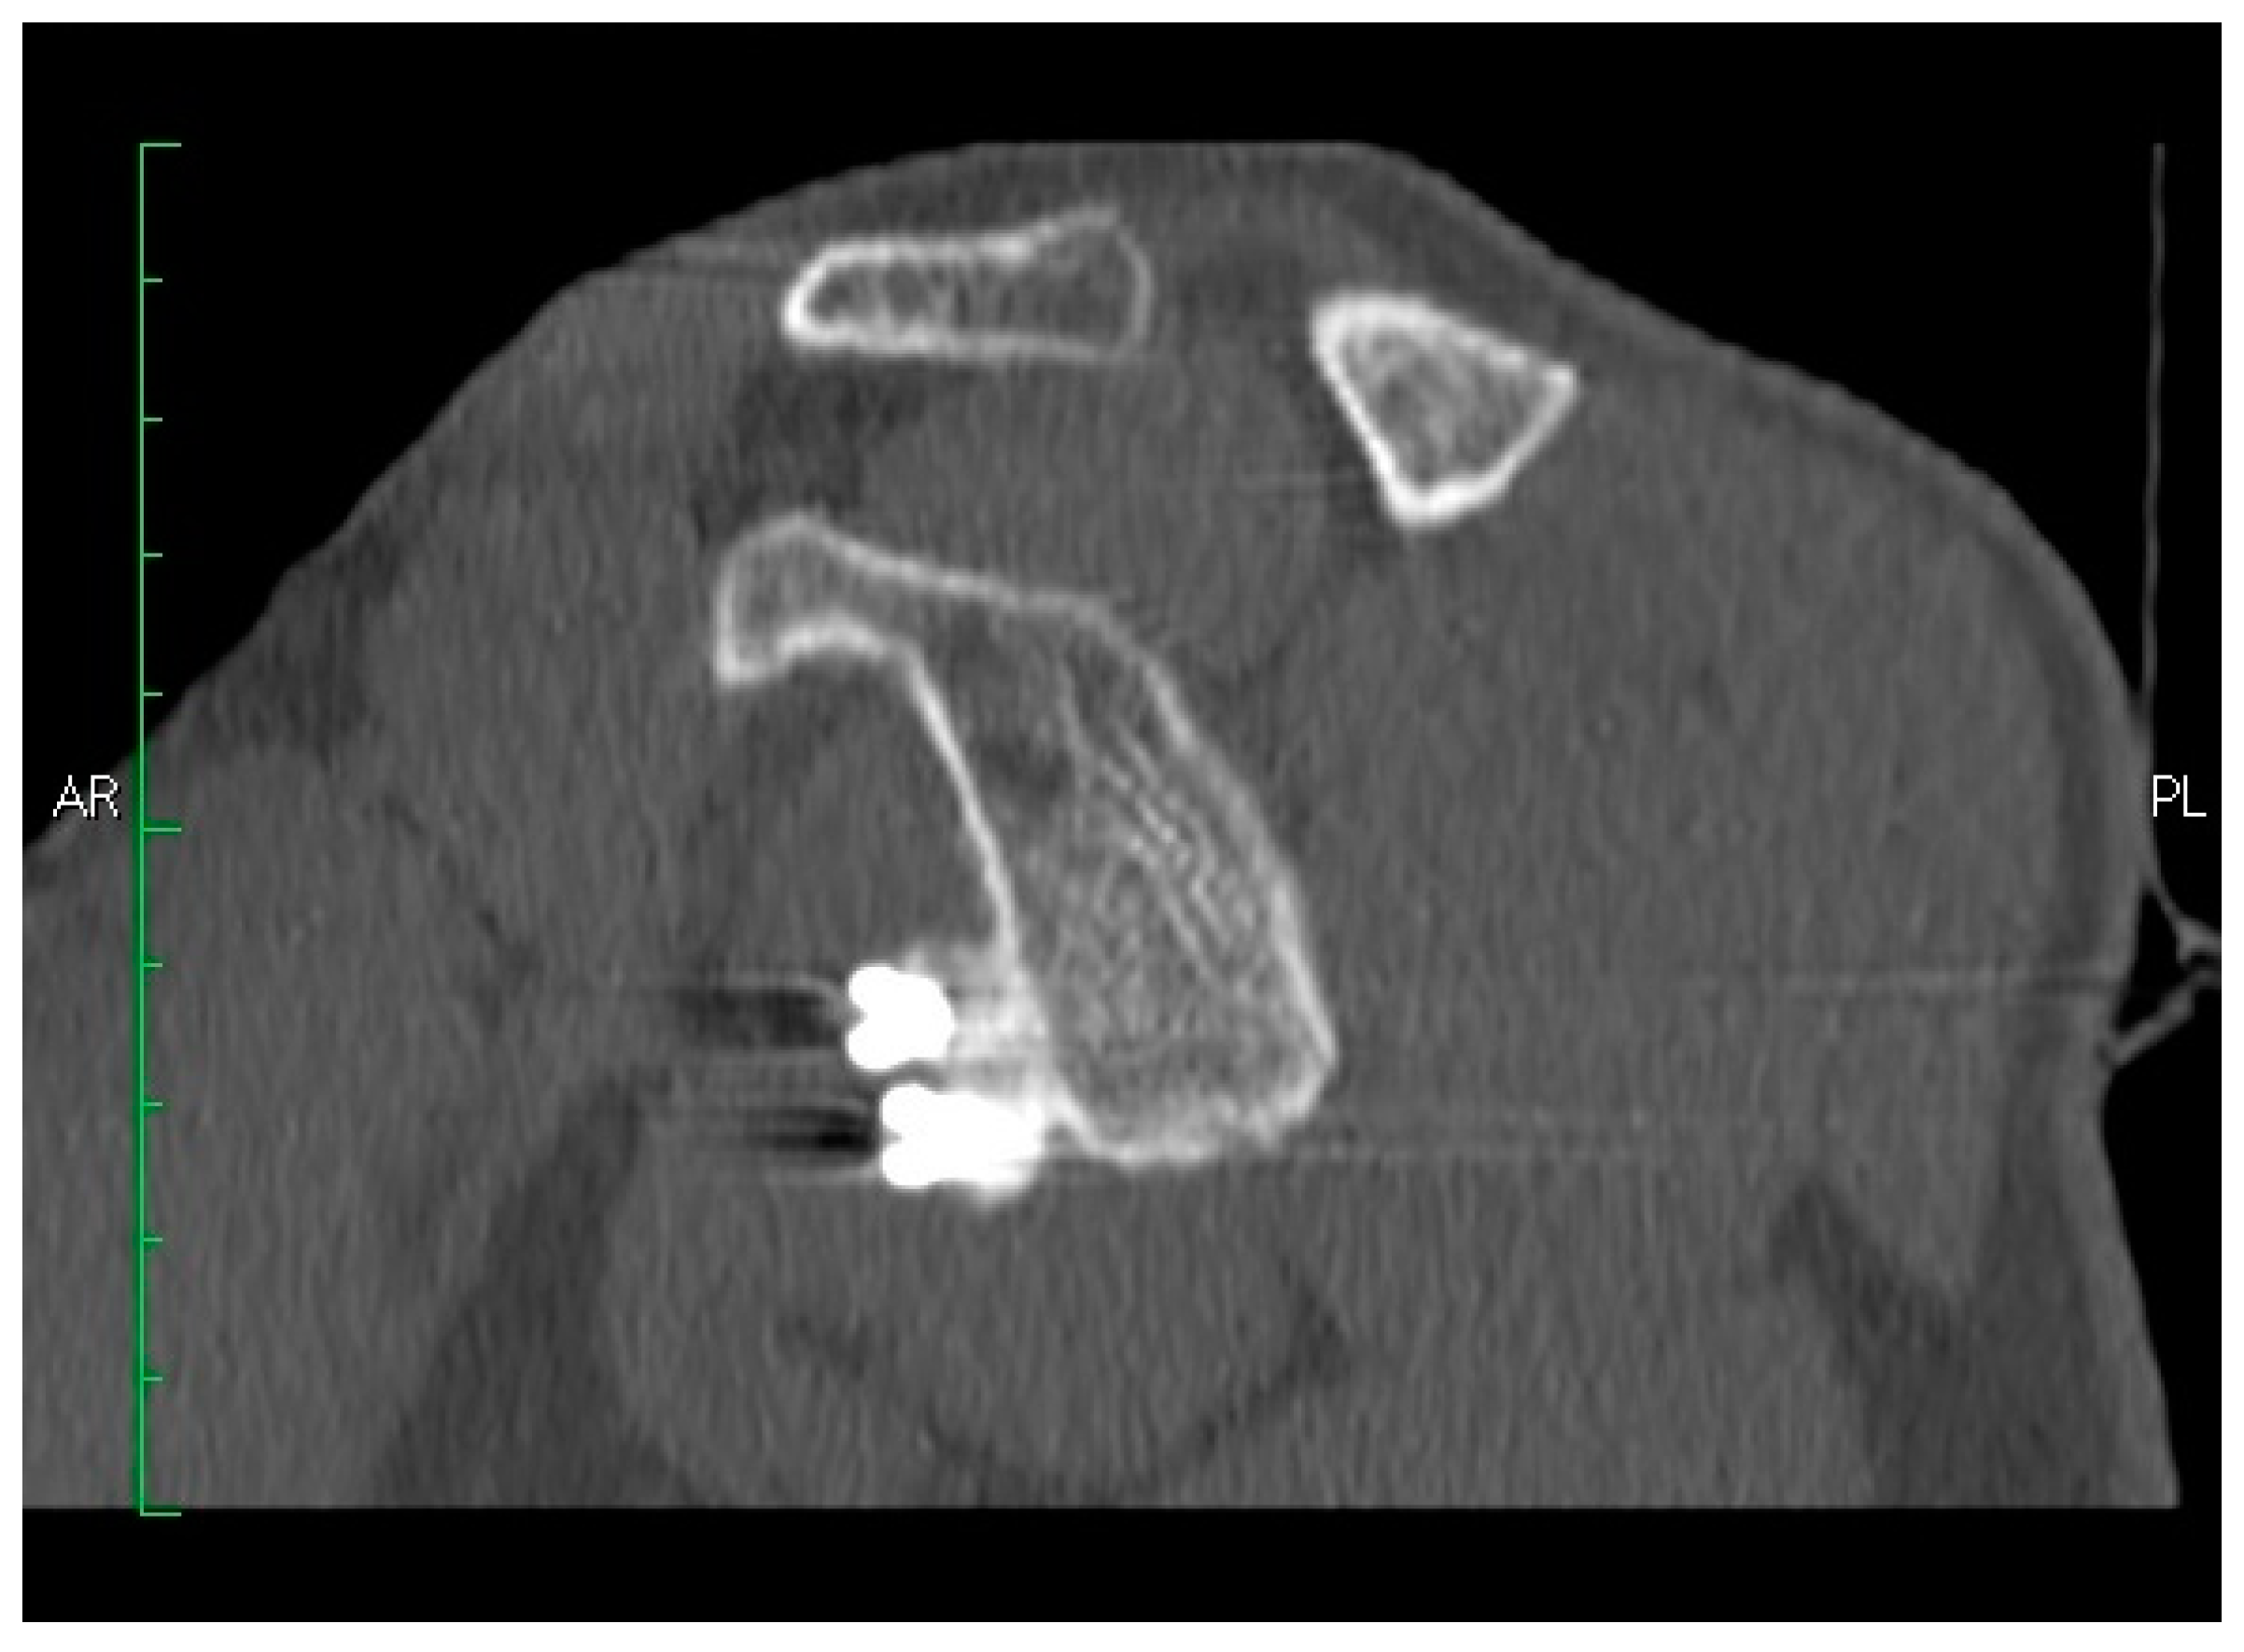

3.3.1. Coracoid Graft Healing

3.3.2. Coracoid Graft Positioning

3.3.3. Screws Angle